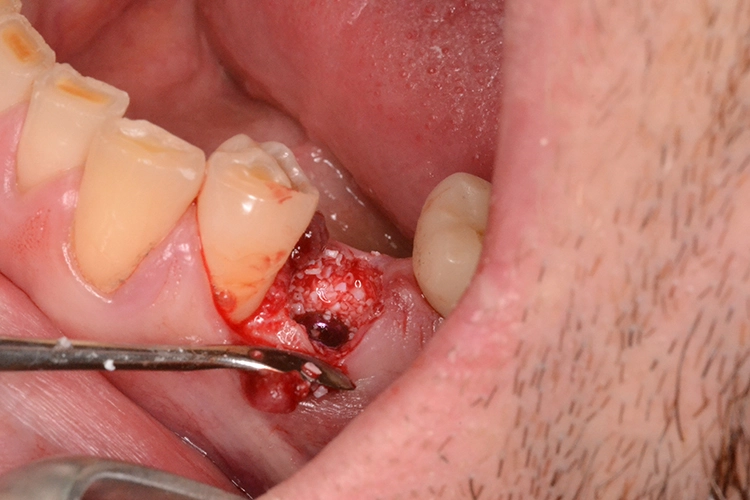

Im präoperativ angefertigten DVT (Abb. 3b und c) zeigte sich um die Wurzelspitze ein chronisches Entzündungsgeschehen, welches die vestibuläre Lamelle im apikalen Wurzelbereich des Zahnes 23 komplett aufgelöst hat. Da jedoch der Bereich direkt apikal von 23 nicht vom Geschehen betroffen war, fiel die Entscheidung zur Sofortimplantation auch, da der Patient blutverdünnende Medikamente einnehmen musste, welche durch Kombination von Extraktion und Implantation nur einmal abgesetzt werden mussten. In diesem Fall war aufgrund des Knochendefektes die Bildung eines Volllappens mit Entlastung unumgänglich.

Anschließend wurde der Knochendefekt mit kortikospongiösem Knochengranulat aufgefüllt und mit einer langsam resorbierenden Kollagenmembran versorgt (Abb. 3e und f). Das OP-Gebiet musste im Anschluss aufgrund der Augmentation vollständig gedeckt werden (Abb. 3g).